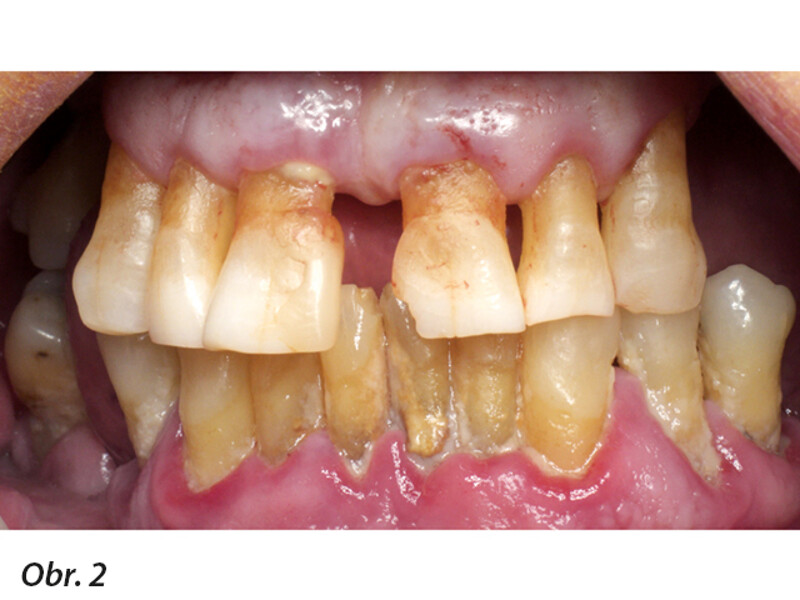

Plně digitální Pro Arch protokol